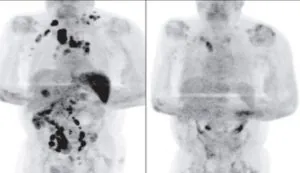

While both non-Hodgkin’s and Hodgkin’s lymphoma effect the lymphatic system, they often impact different parts of the system. Hodgkin’s lymphoma typically occurs in the lymph nodes found in the neck, chest, or underarms. From there, it often progresses in a predictable fashion moving from one group of lymph nodes to the next. Progressing in such an orderly fashion allows the cancer to be detected and treated at an early stage. Hodgkin’s lymphoma is recognized as one of the most treatable cancers, with over 90% of patients surviving more than five years. Non-Hodgkin’s, however, often arises in various parts of the body. It can surface in similar lymph nodes as Hodgkin’s lymphoma, or even in the groin and abdomen. Because of this, most cases of non-Hodgkin’s lymphoma is diagnosed at an advanced stage.